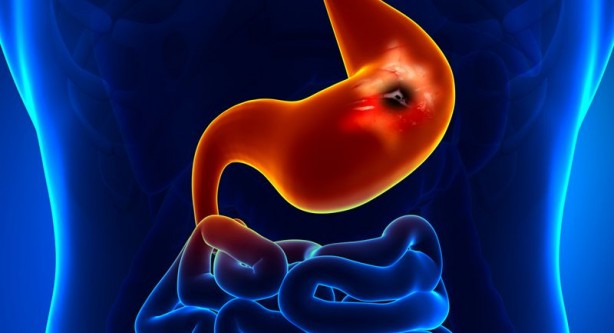

İçerdiği vitaminler sayesinde birçok faydası olan ve bu nedenle de sürekli tükettiğimiz limon suyu aslında çok da masum değil. Uzmanlar limon suyunun zararlarına ilişkin önemli araştırmaları ortaya koydu. İşte limon suyunun sebep olacağı rahatsızlıklar...